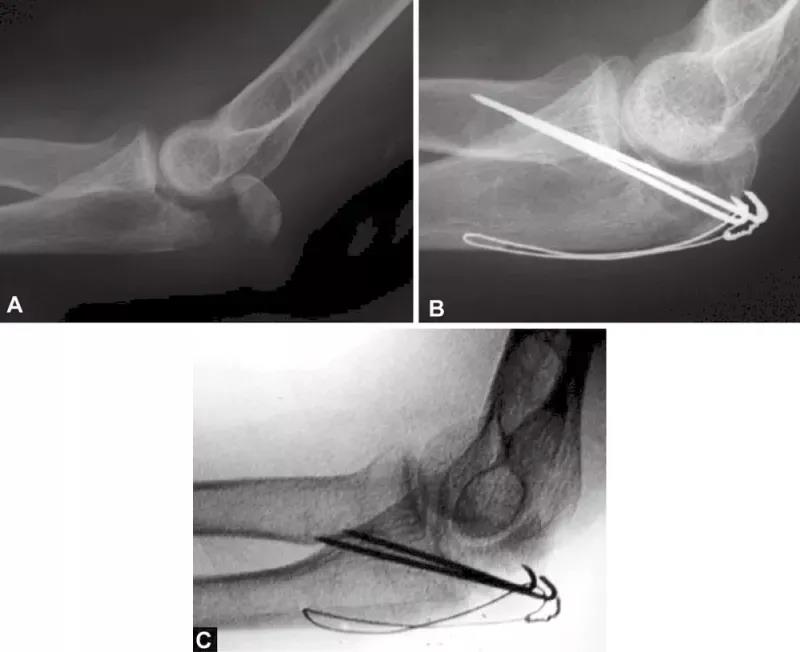

图1A~C(A)关节压缩骨折不易觉察,有经验的医生会注意到从冠状突到鹰嘴尖的关节间隙增宽而得出诊断;(B)如果没有的观察力,医生甚至会在术中X线片检查中都漏诊明显的压缩骨折。医生的注意力完全集中在检查植入物的位置上,因此容易忽略关节不一致;(C)术后摄片显示压缩骨折未复位